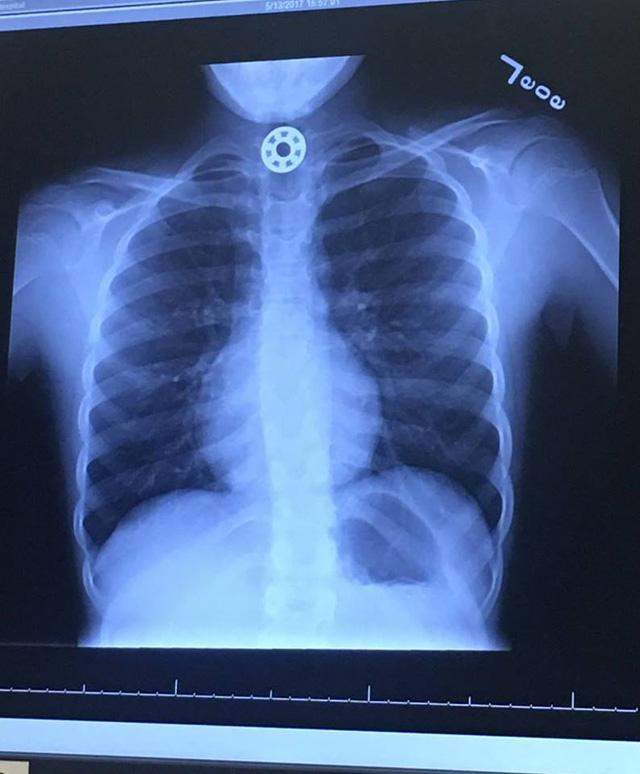

Bé Britton sau đó được chuyển tới Bệnh viện Nhi bang Texas để chụp X-quang, và tại đây người ta mới xác định được vị trí của nó là nằm tại thực quản của cô bé.

Cục kim loại hình tròn nằm trong đồ chơi Fidget Spinner bị cô bé nuốt và mắc tại thực quản. Ảnh: Dân Trí